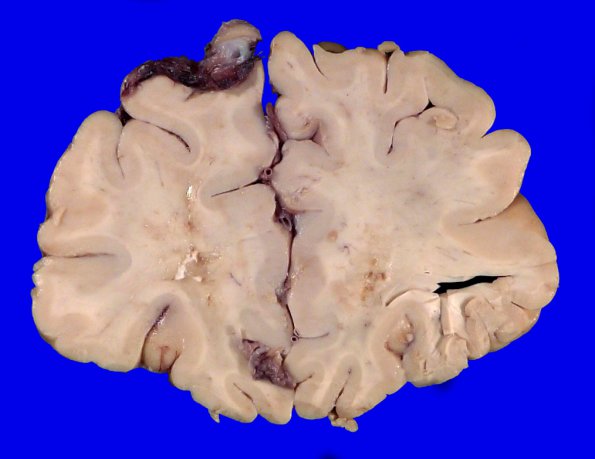

Washington University Experience | MYELIN (NON-IMMUNE MEDIATED) | Retinal Vasculopathy with Cerebral Leukoencephalopathy (RVCL, TREX1 Mutation) | 17B4 RVCL (Case 17) Gross _6

174,5 Areas of discoloration and calcifications involving the frontal lobe deep white matter.